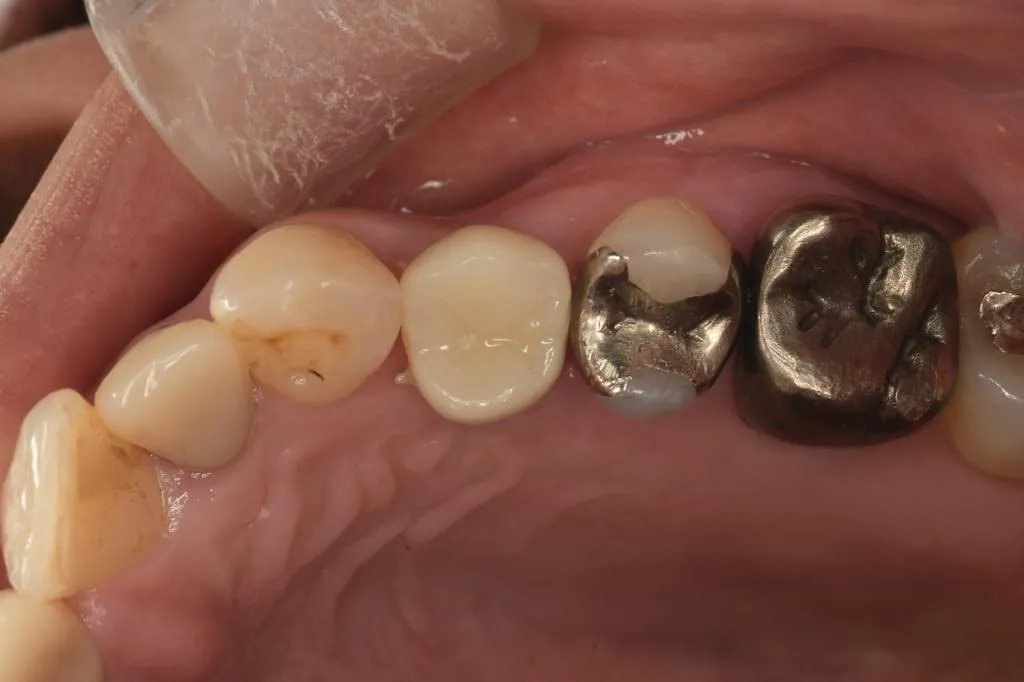

インプラント治療症例①

インプラント治療症例②

インプラント治療症例③

インプラント治療症例④

インプラント治療症例⑤

インプラント治療症例⑥

歯周病などで骨が少なくなった患者さんに対して行う、骨を再生させる処置(ソケットプリザベーション)